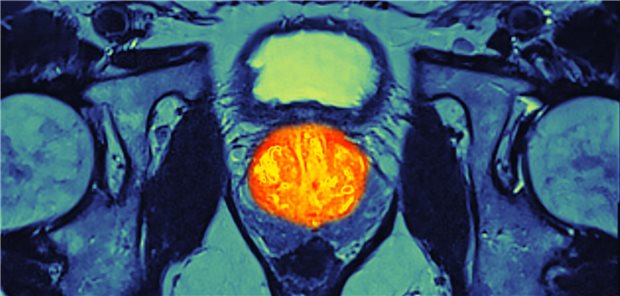

Prostatakarzinom-Früherkennung

Hannover. Erst seit wenigen Wochen gibt es die neue S3-Leitlinie „Prostatakarzinom“. Da Männer einer aktuellen Langzeitstudie zufolge die meiste Information zur Prostatakrebs-Vorsorge von ihren Hausärztinnen und Hausärzten beziehen, die die Messung des Prostata-spezifisches Antigens (PSA) teils kritisch sehen, macht es Sinn, sich damit zu befassen, was dazu in der interdisziplinären Leitlinie steht.

Bestätigt sich ein Wert ≥3 ng/ml nach drei Monaten, ist der weitere Weg vorgezeichnet: „Ab zum Urologen!“ Dann erfolge in der Regel eine Magnetresonanztomografie zur weiteren Diagnostik, sagte Braun. „Inwieweit das jetzt in die Früherkennungs-Richtlinien Einzug halten wird, bleibt abzuwarten.“